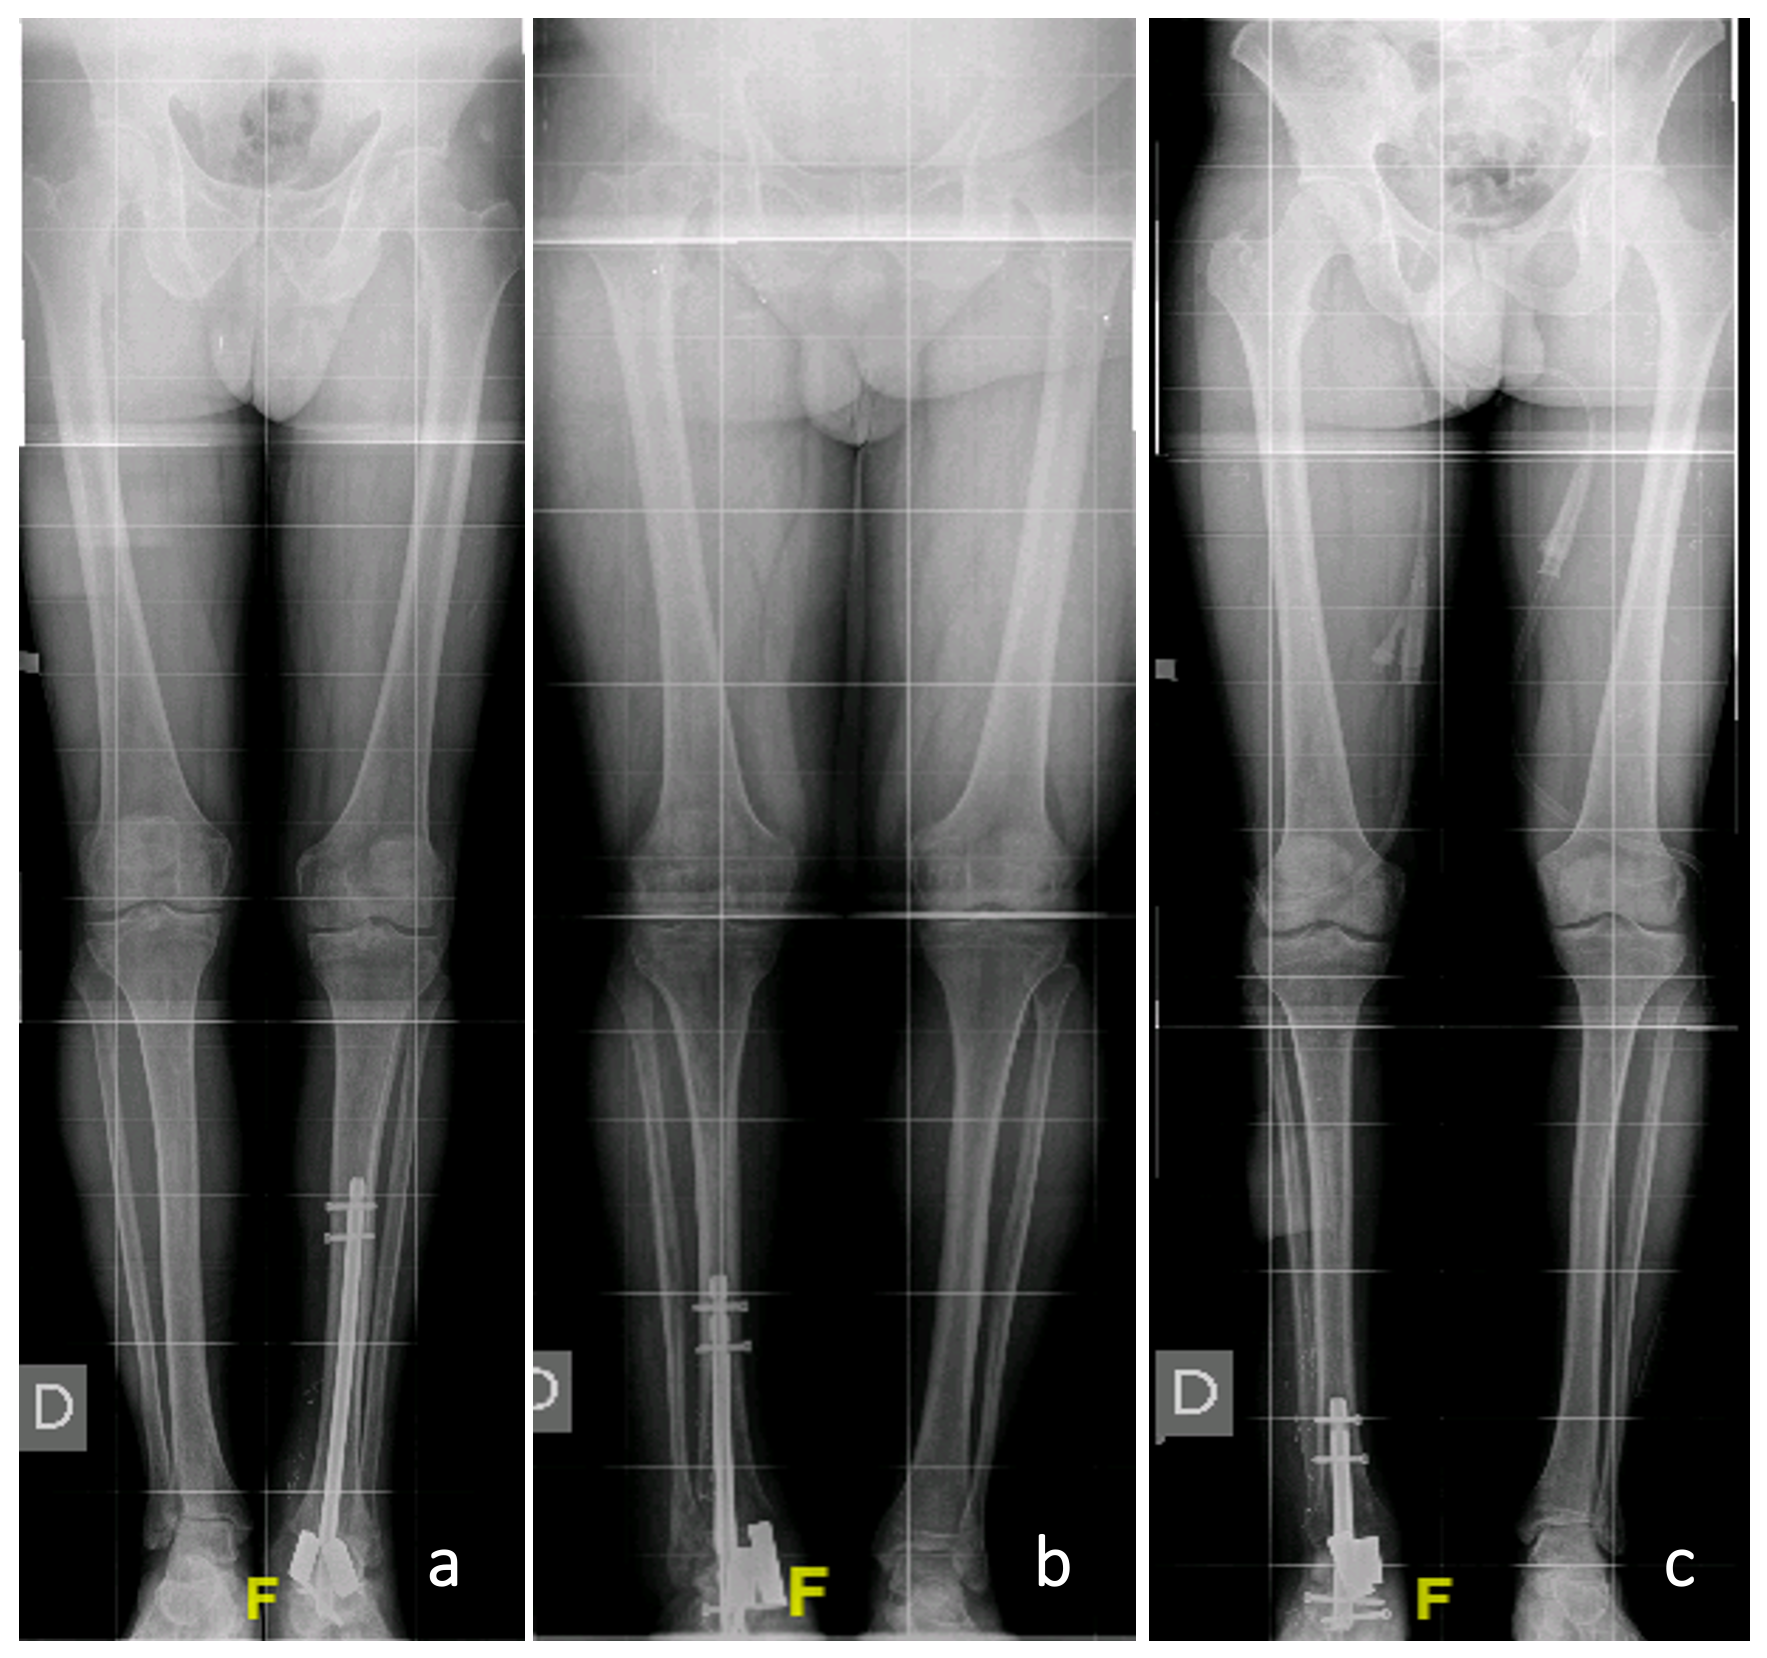

Total fusion was seen in the 1-year follow-up CT scan control, and a correct axis may be seen in X-rays, with no significative leg-length discrepancy (Figs. 3 and 4).

https://jbji.copernicus.org/articles/10/419/2025/jbji-10-419-2025-f03

Figure 3Postoperative alignment. Standing long-leg images corresponding to cases 1 (a), 2 (b), and 3 (c), respectively